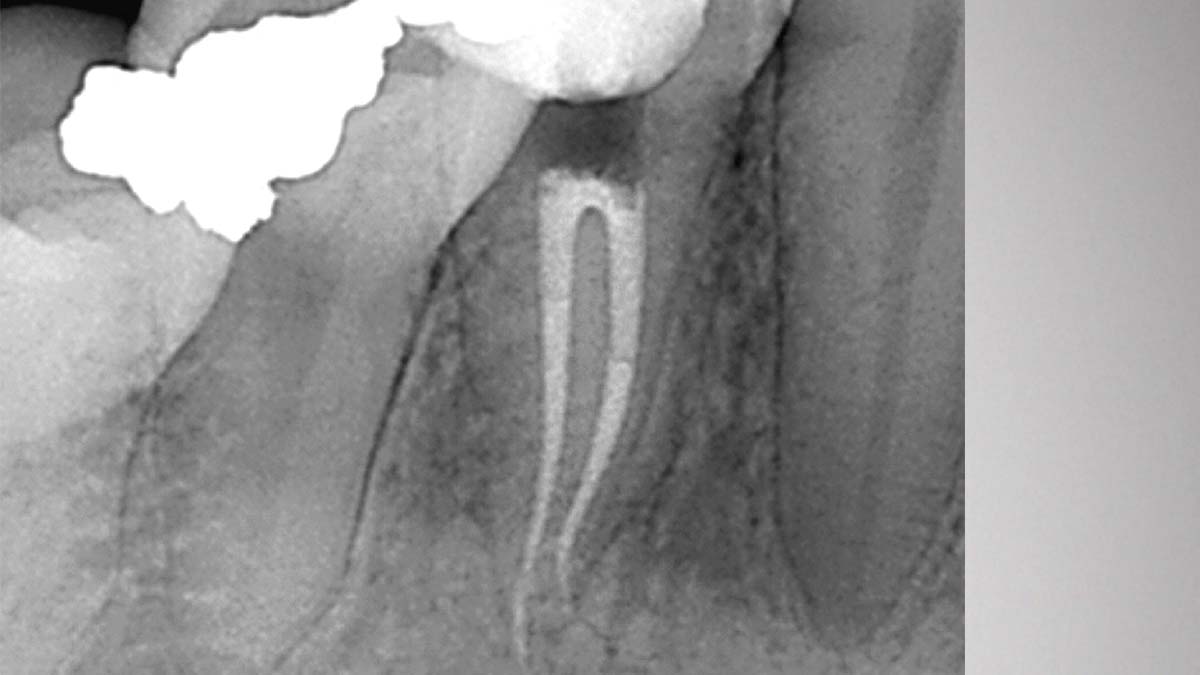

On the left: Using different formulations of gutta-percha in one case can cause varying degrees of opacity.

Image courtesy of Dr. Phillip Bell, Mooresville, NC